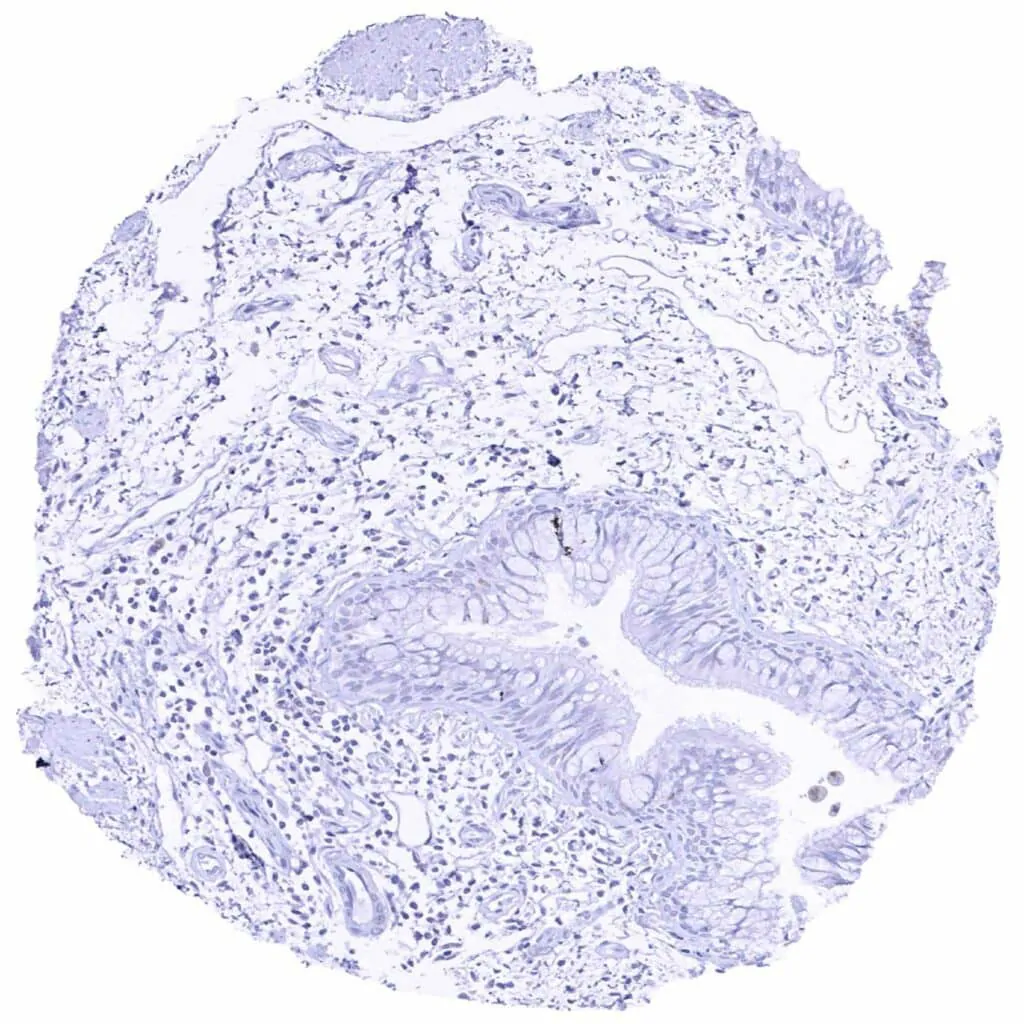

Aorta, media

Colon descendens, muscular wall

Heart muscle

Urinary bladder, muscular wall